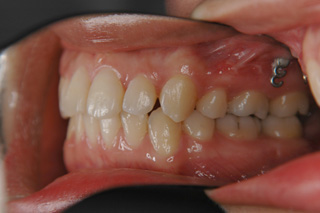

(上下顎前突/上下顎小臼歯抜歯)

装置撤去です。動的処置は2年弱でしたので、歯の移動させた距離で考慮すると、比較的短い治療期間でした。極めてよい咬合状態が得られたと思います。いずれも強い固定源を利用した結果の成果と考えられます。まだ、オーソアンカー SMAPシステム がそのまま残っているのが見えますが、もう必要ないので撤去して貰う予定です。今後は保定治療に移行し、数年にわたって咬合の安定状態を管理していきます。